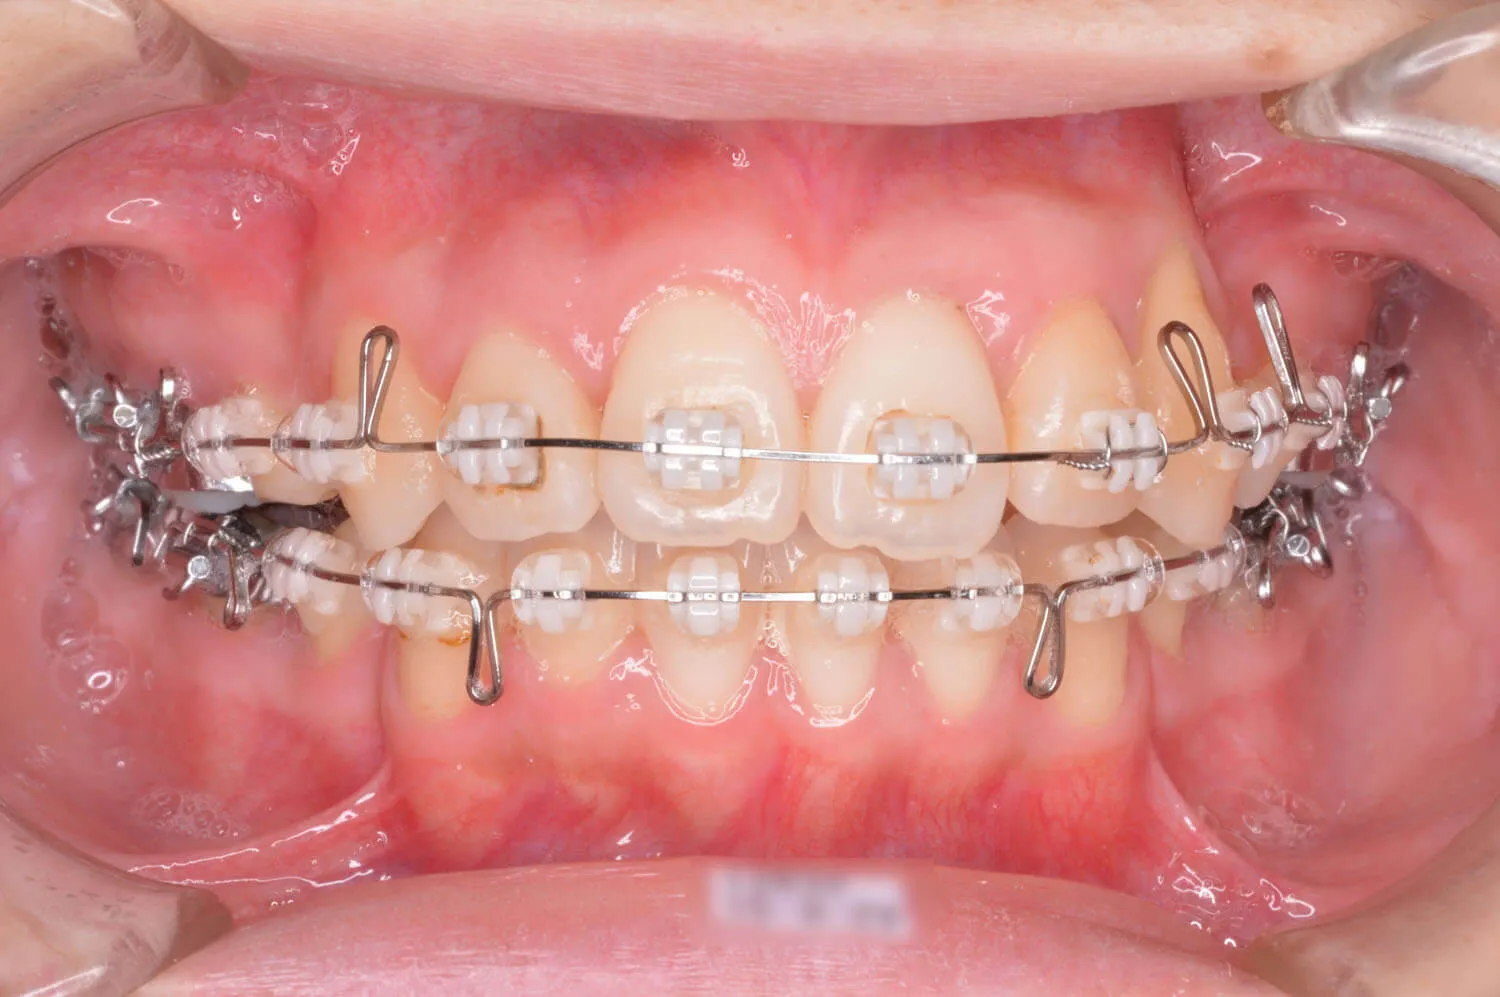

左上の糸切り歯が完全に歯列に並びました。

開咬状態も改善されてきました。